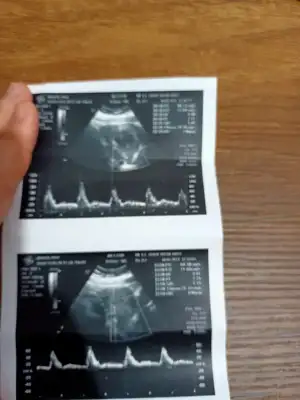

Ikra meyra Ikra meyra merhabaaa Canım :) Arkadaşımın bebisinin fotosunu atiyorum.Sana zahmet tahminde bulunabilirsen çoooook sevinirim :) Şu an 12+2 :)

• IMG-20210517-WA0002.webp

• IMG-20210517-WA0001.webp

• IMG-20210517-WA0000.webp